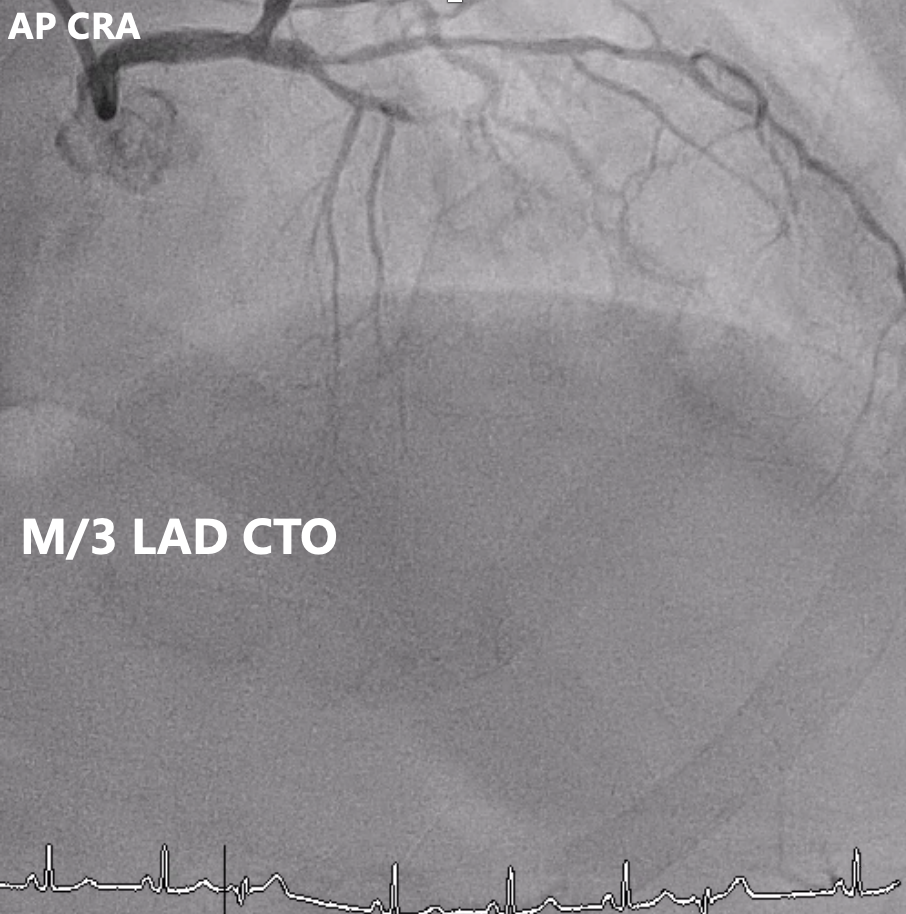

Relevant Catheterization Findings

Angiography showed multivessel atherosclerosis with the LAD being the most critical lesion. The mid LAD had tubular eccentric 70–80% stenosis with a Medina (0,1,1) bifurcation and a mid-segment CTO (~2 cm, blunt end). DB1 had 70–80% ostial stenosis with 50–70% diffuse disease, and DB2 had a short CTO with distal collateral flow from DB1. Other vessels had non-critical or moderate diffuse disease.